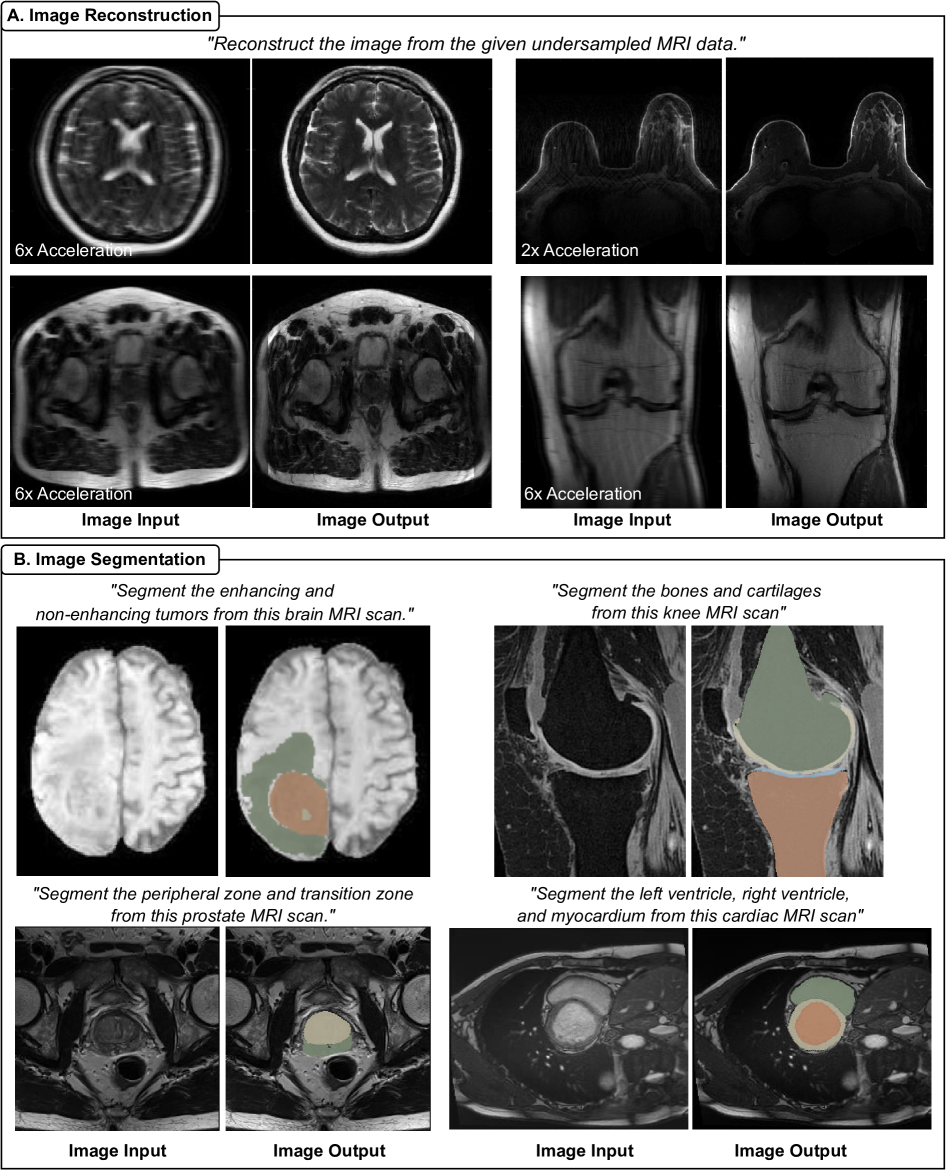

Refer to caption

Figure 3: Qualitative results of OmniMRI on MRI reconstruction and segmentation tasks. (A) Image reconstruction. OmniMRI restores high-fidelity images from undersampled inputs across diverse anatomies, including the brain, breast, prostate, and knee. (B) Image segmentation. OmniMRI delineates anatomical and pathological. Examples include segmentation of enhancing and non-enhancing brain tumors, knee bones and cartilages, prostate peripheral and transition zones, and cardiac chambers and myocardium.

MRI Reconstruction OmniMRI demonstrates robust capability in reconstructing high-fidelity images from undersampled MRI acquisitions across diverse anatomies by following the instruction: “Reconstruct the image from the given undersampled MRI data.” As illustrated in Figure 3A, the model consistently restores fine anatomical detail and suppresses undersampling artifacts across varied use cases.

• Brain: Accurately reconstructs fine structural details from 6× accelerated scans, preserving cortical and subcortical features.

• Breast: Recovers clear tissue boundaries under 2× acceleration, supporting lesion visibility.

• Prostate: Maintains soft-tissue contrast even with 6× acceleration, critical for delineating glandular structures.

• Knee: Reconstructs sharp cartilage–bone interfaces under 6× acceleration, ensuring musculoskeletal interpretability.

Across all examples, aliasing artifacts present in the undersampled inputs are effectively suppressed, yielding images with preserved diagnostic quality and interpretability. These results highlight OmniMRI’s generalizability across anatomies, acceleration factors, and clinical use cases.

Image Segmentation OmniMRI demonstrates robust capability in segmenting diverse anatomical structures and pathological regions across multiple organ systems by following organ-specific instructions. As illustrated in Figure 3B, the model accurately delineates:

• Brain: Enhancing and non-enhancing tumor regions with precise spatial boundaries.

• Knee: Bony structures and cartilaginous tissue, critical for musculoskeletal assessment.

• Prostate: Peripheral and transition zones, supporting cancer localization.

• Heart: Cardiac chambers and myocardium with well-defined borders. Across these examples, the predicted masks exhibit sharp boundary definition and anatomical fidelity, maintaining alignment with clinical landmarks.

The consistency of segmentation performance across heterogeneous organs and tissue types of underscores OmniMRI’s ability to generalize segmentation instructions, bridging applications from neuroimaging to musculoskeletal, body, and cardiac MRI.